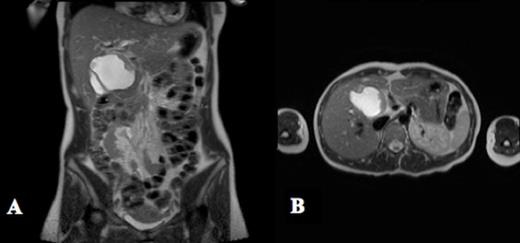

A case of cholangiocarcinoma in an unresected choledochal cyst with local invasion into pancreas and lack of nodal involvement in a total of 10 resected lymph nodes is presented. A 26 year old female presented to our surgical oncology clinic for evaluation of a Type I choledochal cyst. The cyst was identified incidentally by ultrasound seven years prior during the patient’s first pregnancy. A computed tomography (CT) scan demonstrated a 3cm X 8 cm dilated bile duct. A magnetic resonance cholangiopancreatogram (MRCP) was performed and demonstrated a fusiform dilation of the extrahepatic common bile duct measuring at least 7.4 x 4.8 x 6.2 centimeters and enhancing soft tissue polypoid mass arising from the medial wall of the cyst that is concerning for malignancy but no sign of metastatic disease (see figure 1). Resection was recommended at the time but patient opted to monitor growth and delayed surgery. She denied jaundice, acholic stools, vomiting, nausea or fever but did report occasional left upper quadrant pain. A repeat MRI (magnetic resonance image) in 2011 demonstrated a seven centimeter fusiform choledochal cyst abutting the pancreas with an aberrant pancreatic duct and a concerning solid component at the anteriomedial aspect of the cyst. There was no evidence of adenopathy or infiltration of surrounding tissue.

MRCP shows a fusiform dilation of the extrahepatic common bile duct measuring 7.4 x 4.8 x 6.2 cm in the axial (A) and transverse planes (B). There is an enhancing soft tissue mass with a thickness of 1.1 cm protruding into the lumen of the cyst that is concerning for malignancy